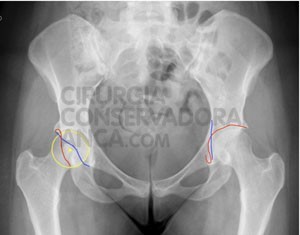

fig. 5: “coxa profunda” bilateral com cobertura excessiva da cabeça femoral numa doente de 28 anos. Após cirurgia (imagem da direita) observamos plastia extensa do acetábulo, permitindo aumentar a mobilidade das ancas e desta forma melhorar a qualidade de vida. Repare-se na correcção das linhas correspondentes ás paredes do acetábulo. Na anca direita foram retirados os parafusos que ainda se observam à esquerda.